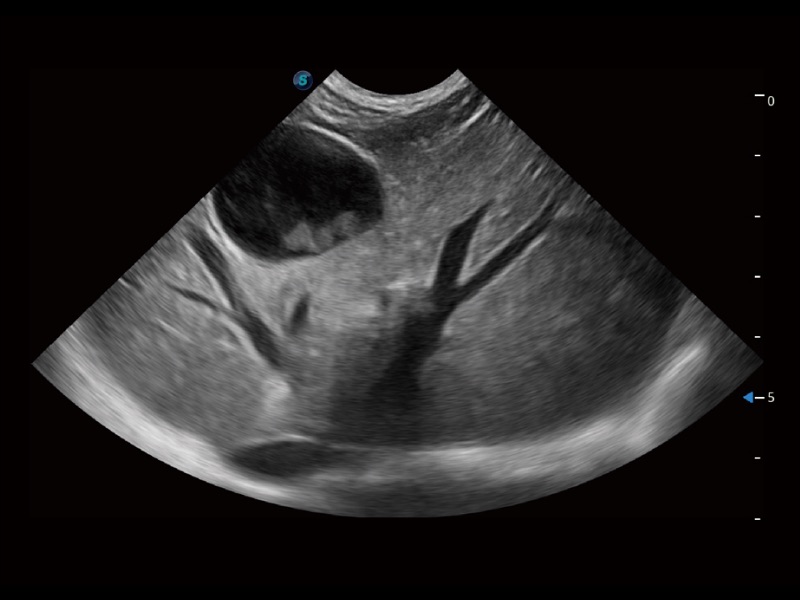

优异的基础图像

ProPet 70 全新的动物超声智能软件和丰富的探头群,为动物医生提供了高清晰度和精细分辨率的图像,无论在宠物、马科、畜牧还是实验室动物等应用中都可以轻松应对,为您的日常工作带来满意的体验。

(犬)肾脏显微血流

(犬)肝脏